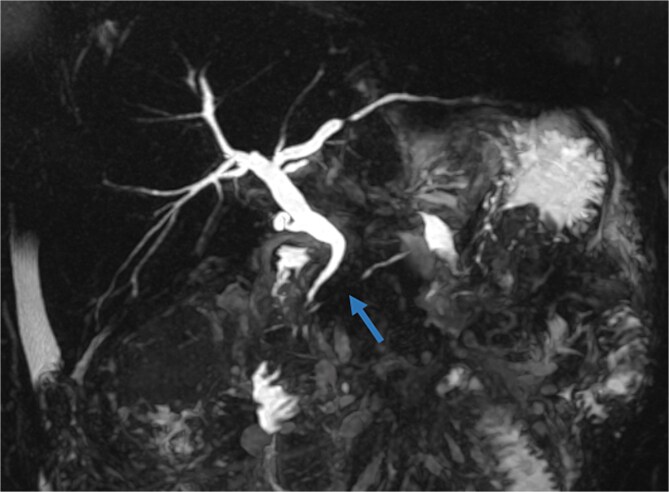

胰管断裂综合征(DPDS)是一种罕见的疾病,其特征是胰管断裂,使活的胰腺组织与胃肠道分离。它常伴随急性或慢性胰腺炎、腹部创伤或胰腺手术,导致导管坏死或解体。DPDS提出了重大的诊断和管理挑战,特别是在延迟发病的病例中。作者报告了一个坏死性胰腺炎后复发性胰液收集的复杂病例,强调了延迟DPDS表现的可能性。先进的成像技术,包括内窥镜超声检查,对比增强CT和MRCP,用于诊断。由于保守治疗失败,我们进行了远端胰腺切除术,解决了这个问题,并防止了感染、败血症或胰瘘等并发症。该病例强调了早期识别DPDS在影像学上的重要性,有助于及时治疗并降低长期并发症的风险。

Disconnected pancreatic duct syndrome (DPDS) is a rare condition characterized by a disruption of the pancreatic duct, separating viable pancreatic tissue from the gastrointestinal tract. It often follows acute or chronic pancreatitis, abdominal trauma, or pancreatic surgery, leading to ductal necrosis or disintegration. DPDS presents significant diagnostic and management challenges, especially in cases with delayed onset. The authors report a complex case of recurrent pancreatic fluid collections after necrotizing pancreatitis, highlighting the potential for delayed DPDS manifestation. Advanced imaging techniques, including endoscopic ultrasonography, contrast-enhanced CT, and MRCP, were used for diagnosis. Due to failure of conservative treatment, a distal pancreatectomy was performed, resolving the issue and preventing complications such as infection, sepsis, or pancreatic fistula. This case underscores the importance of early recognition of DPDS on imaging, facilitating timely treatment and reducing the risk of long-term complications.